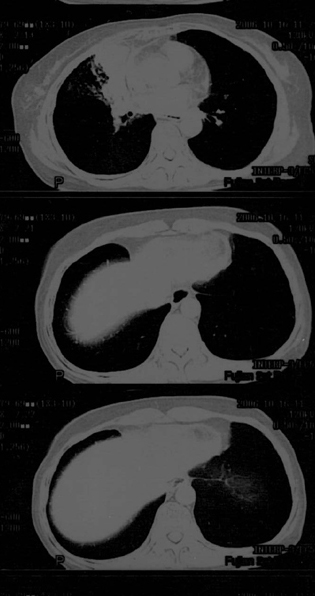

母亲67岁,咳嗽,无血痰。发病已两月余,抗生素无效

传上图片看不清,可是给我的感觉是恶性的,虽然还需跟肺结核相鉴别.

片子不清,右肺下叶像个结核球,右肺上叶需要做个支气管镜检查,除外中心型肺癌。个人意见,其他老师们再看看。